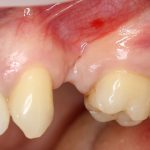

Но, если мы говорим не о поиске истины, а о выборе метода лечения? К примеру, мы столкнулись с распространенной ситуацией:

или вот:

когда атрофия альвеолярного гребня препятствует установке правильных имплантатов в правильное положение (см. Рекомендации по установке имплантов. Часть V).